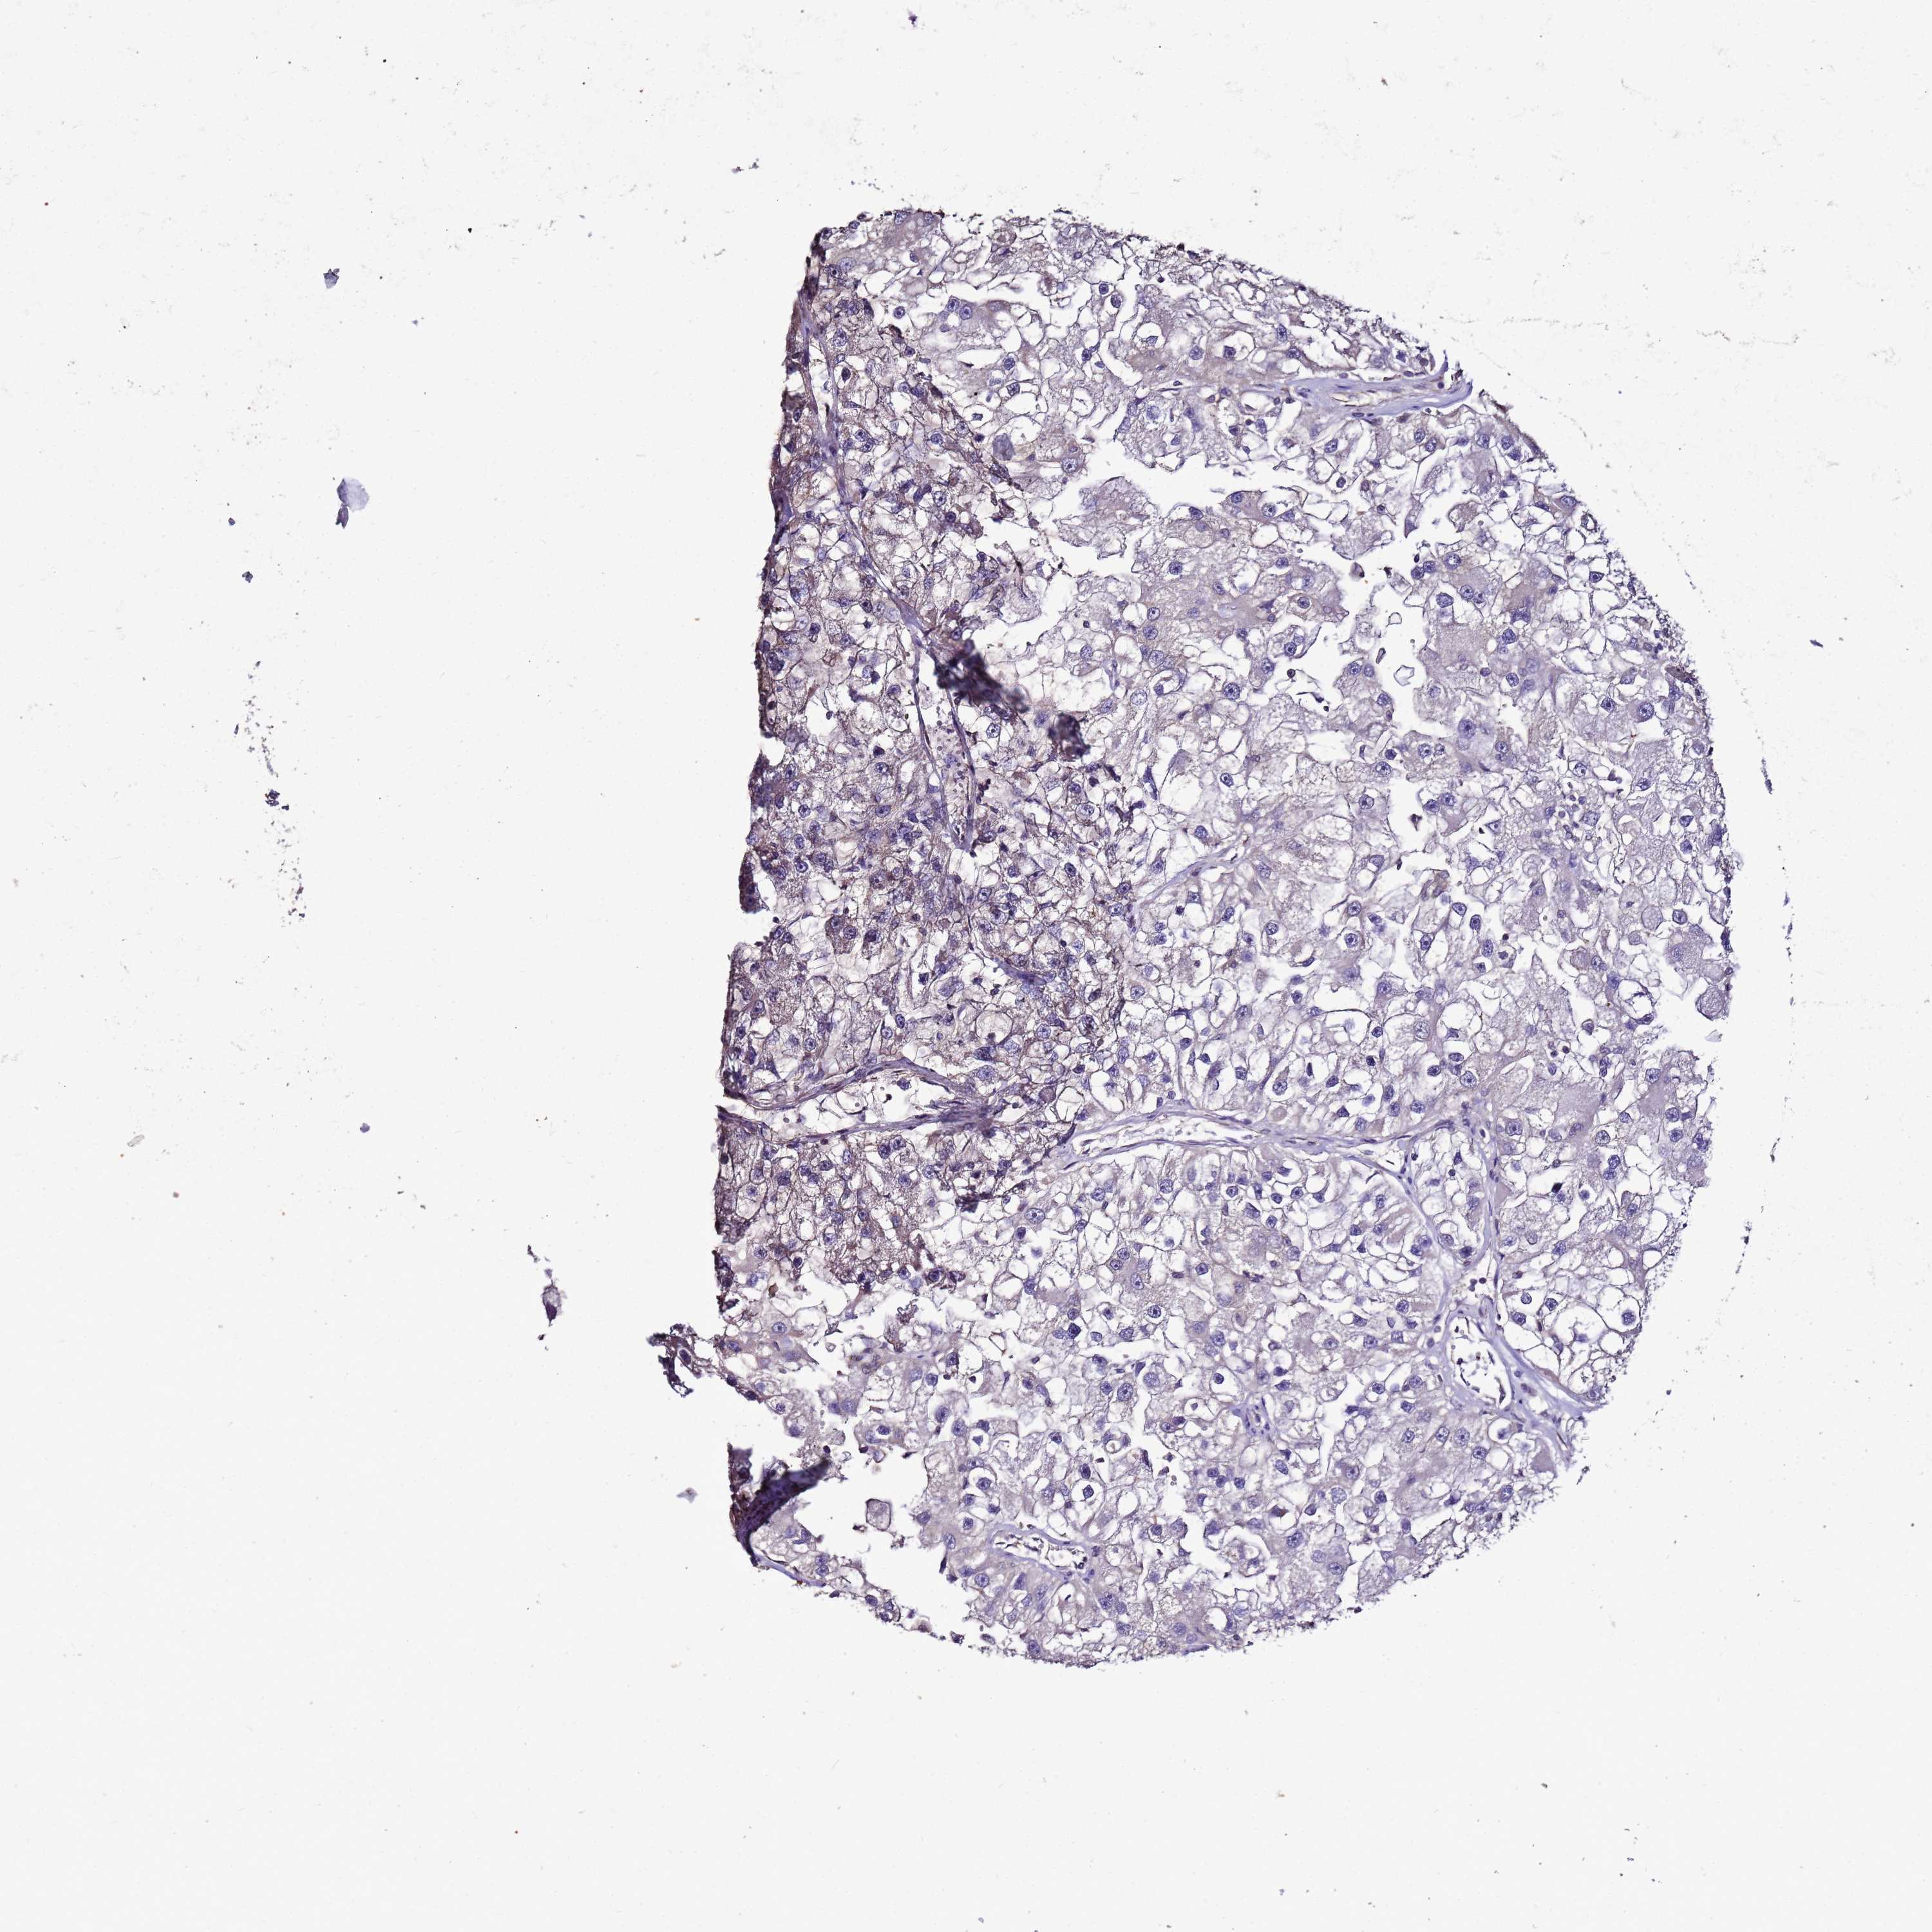

KIDNEY RENAL CLEAR CELL CARCINOMA (VALIDATION) - Interactive survival scatter ploti

ENOPH1 is not prognostic in Kidney Renal Clear Cell Carcinoma (validation)

: 47.23

Average pTPM 39.6

Number of samples 100